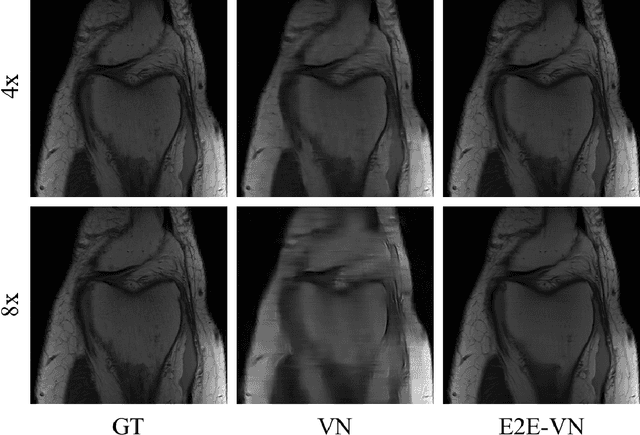

Abstract:The slow acquisition speed of magnetic resonance imaging (MRI) has led to the development of two complementary methods: acquiring multiple views of the anatomy simultaneously (parallel imaging) and acquiring fewer samples than necessary for traditional signal processing methods (compressed sensing). While the combination of these methods has the potential to allow much faster scan times, reconstruction from such undersampled multi-coil data has remained an open problem. In this paper, we present a new approach to this problem that extends previously proposed variational methods by learning fully end-to-end. Our method obtains new state-of-the-art results on the fastMRI dataset for both brain and knee MRIs.